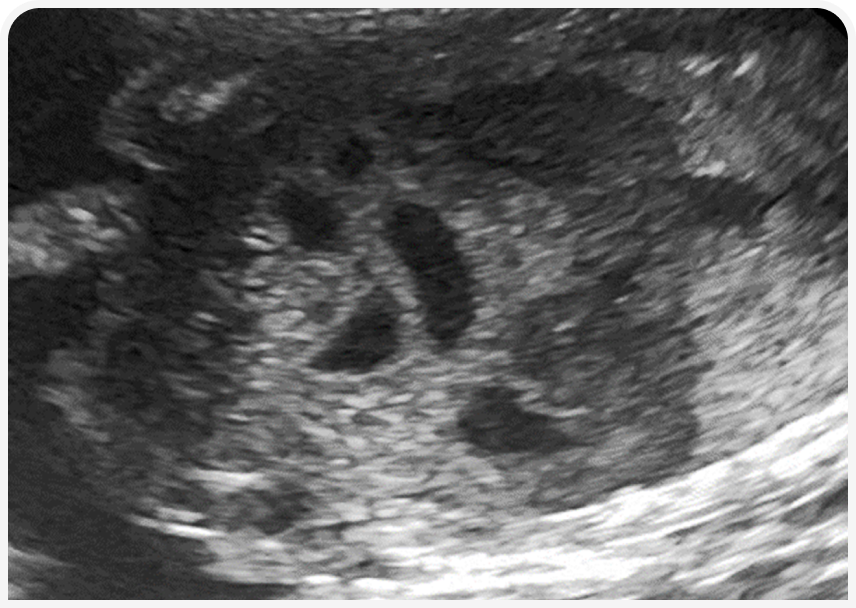

Для диагностики данного состояния оптимально использовать УЗИ. При ультразвуковом исследовании ЖКТ у плода или новорожденного будут выявляться «классические» признаки механической обструкции кишечника — расширение петель кишечника и желудка значительным количеством жидкостного содержимого до места обструкции и нормальная картина без расширения просвета после места обструкции.

Особое значение имеет УЗИ плода на поздней стадии беременности. По опыту автора, врожденную ВКН достаточно точно удается диагностировать у плодов на последней неделе беременности. У плодов при внутриутробном развитии может визуализироваться жидкость только в желудке.

При патологии будет обнаруживаться картина расширения петель тонкого кишечника, что с высокой долей вероятности коррелирует с ВКН на любом уровне ниже пилорического отдела желудка. При сомнениях полезно сравнить картину подозрительного плода и других плодов.